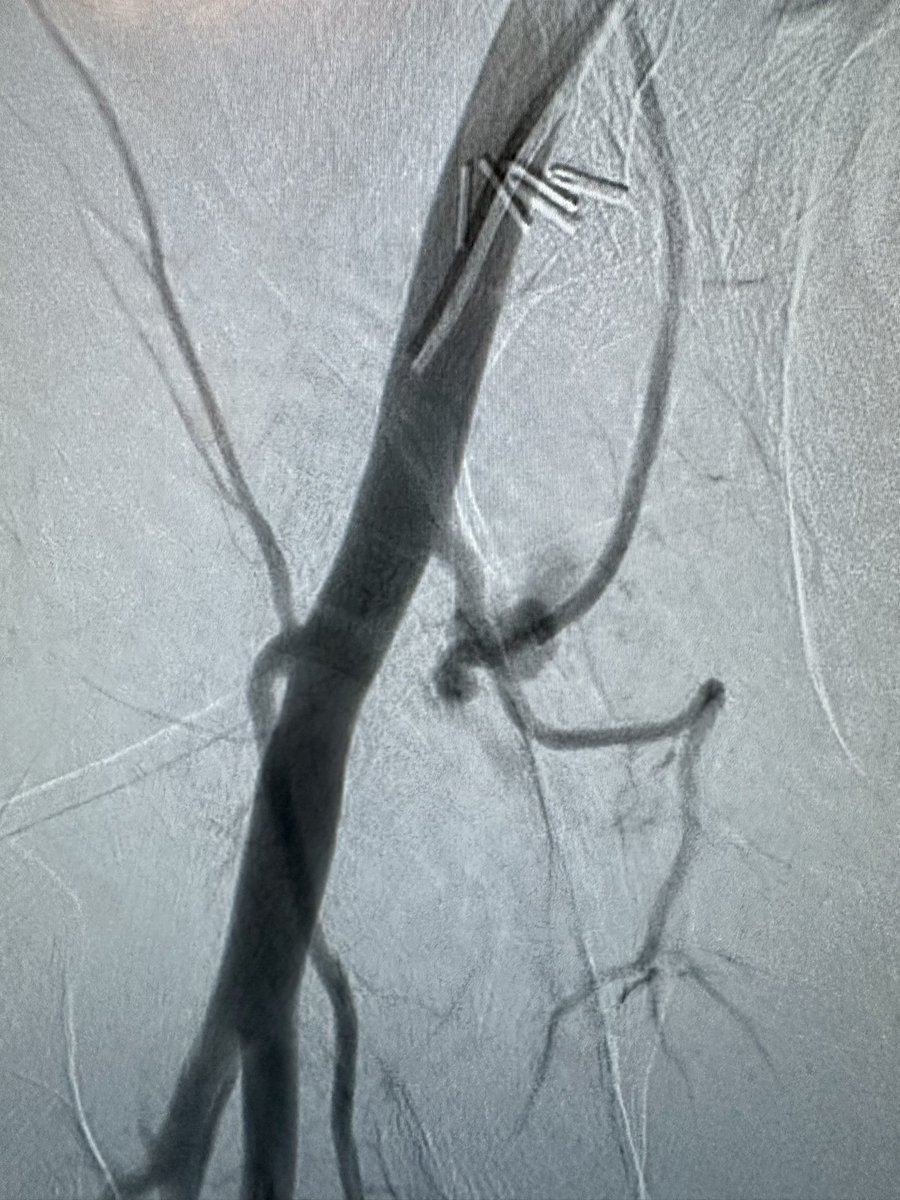

Dear @SIRspecialists, @SIR_ECS, @SIRRFS, #twitir, @FutureVascSurgn, @VascularSVS, @STS_CTsurgery, @ACCinTouch and anyone else who currently or aspires to access groins,

Respect the 👑☠️. #variants

Sincerely,

@DrDukesVIR